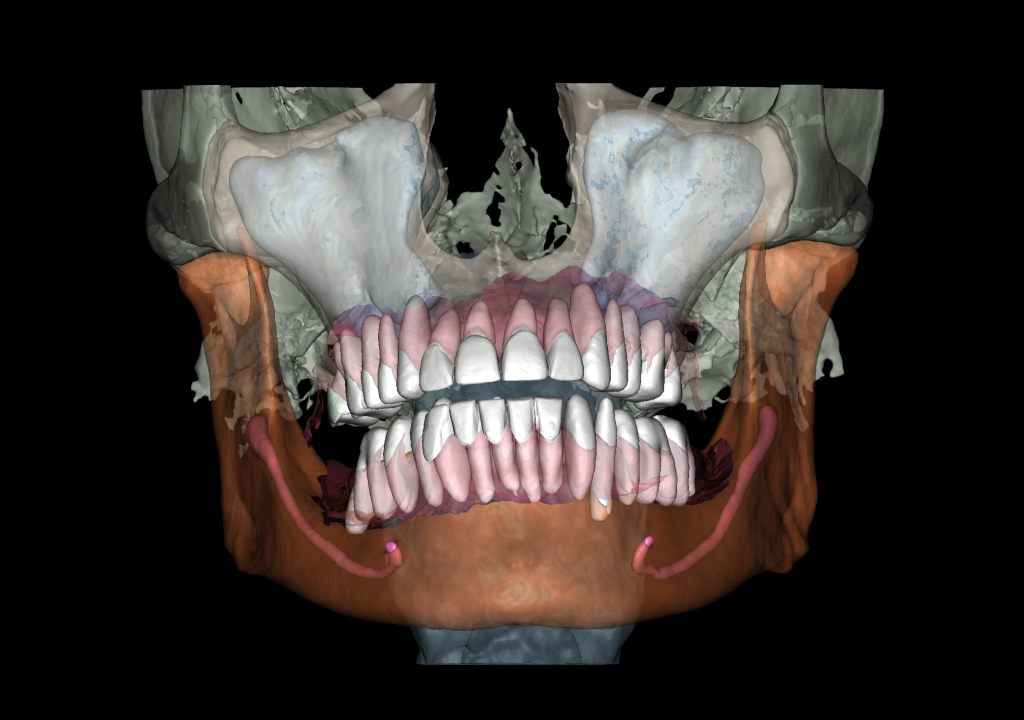

Combining DICOM data and intraoral scans in Diagnocat STL module allows for the creation of 3D models

Based on these data, stereolithographic models were created and a surgical template for gingivectomy was planned